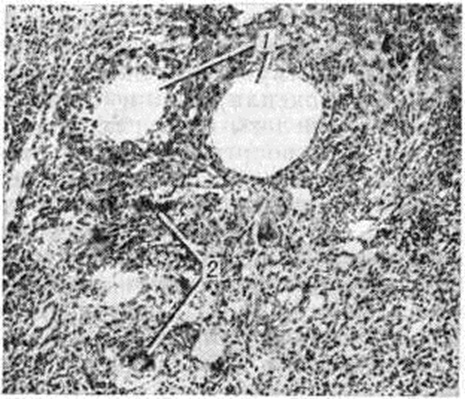

Морфологически черты воспалительной реакции универсальны и не зависят от места введения и природы маслянистого вещества. Во всех случаях Липогранулема — это очаг хронический воспаления, особенностью которого являются мелкие кисты, выстланные крупными клетками эпителиоидного типа и содержащие жировые массы (рисунок, 1). Между полостями наблюдается инфильтрация ткани различными элементами грануляционного ряда, среди которых обнаруживаются гигантские многоядерные клетки — липофаги (рисунок, 2). В инфильтрате нередко встречаются образования, по строению напоминающие туберкулёзные бугорки. В центре дермонекротической Липогранулема видны бесструктурные массы распадающейся фиброзной и жировой ткани, которые могут прорываться наружу с образованием свищей.